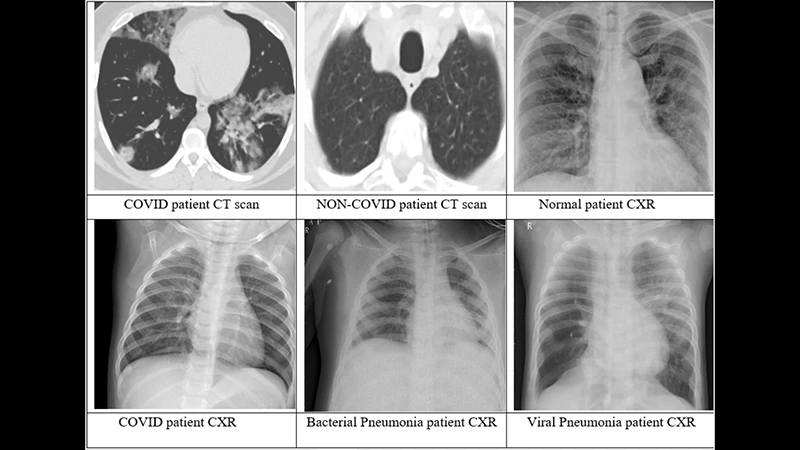

• X-ray Image: An X-ray shows a 2D view where all the internal structures are superimposed on top of each other. For example, on a chest X-ray, the ribs, lungs, heart, and spine are all layered together. This can make it difficult to see small details behind other organs.

• CT Image: A CT scan eliminates this overlap. It provides a clear, cross-sectional view of one "slice" of the body at a time, as if you were looking at a single slice of a loaf of bread. This allows doctors to see the precise size, shape, and location of organs and abnormalities with incredible clarity.

A side-by-side comparison of a chest X-ray and a single CT slice, showing the superior detail of the CT.